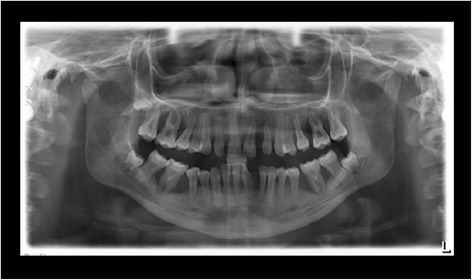

At the age of 16 years the patient returned. The clinical examination revealed generalized increased tooth mobility and gingival hyperplasia (Figure 3). The patient complained about severe halitosis and impaired aesthetics due to the gingival hyperplasia. Compared to the clinical and radiological assessment at 13 years of age, a progression of attachment and bone loss was noted (Figures 4 and 5). A microbiological analysis of supra- and subgingival plaque [14] revealed the intraoral presence of Porphyromonas gingivalis, Eikenella corrodens, Prevotella intermedia, Prevotella nigrescens, Tannerella forsythensis, and Treponema denticola. Aggregatibacter actinomycetemcomitans was not detected. A combined sample of supra- and subgingival plaque before non-surgical periodontal therapy was taken from the deepest periodontal pocket in each sextant and microbial species were detected by polymerase chain reaction (PCR).

Figure 4.

Panoramic radiograph at the age of 16 years: three years following conventional quadrantwise supra- and subgingival debridement without any supportive periodontal therapy.